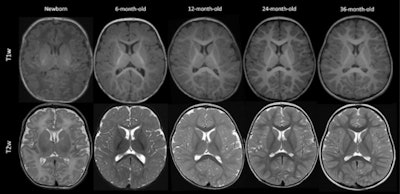

Axial T1-and T2-weighted (T1w and T2w, respectively) MRIs of infants and young children with normal myelin maturation at the level of corpus callosum and lateral ventricles. Note that the images are resized to keep the focus only on progression of myelin maturation at different months. (A) A term newborn with meconium aspiration syndrome who underwent imaging to rule out ischemia, infarction, or hemorrhage. (B) A 6-month-old infant with a history of asphyxia and sinus vein thrombosis at birth but with normal development. (C) A 12-month-old child with an ocular hemangioma who underwent imaging to rule out intracranial pathology. (D) A 24-month-old child with headache for 2 months. (E) A 36-month-old child with a history of focal seizures, imaging is performed to rule out structural changes. Images and caption courtesy of the RSNA.The group tested the three models on an internal dataset and on two external sets (these external sets included information from the National Institutes of Health pediatric brain MRI database and the Developing Human Connectome Project database). The team then evaluated the models' performance for assessing myelin age in months using mean absolute error (MAE) and Pearson correlation coefficients.